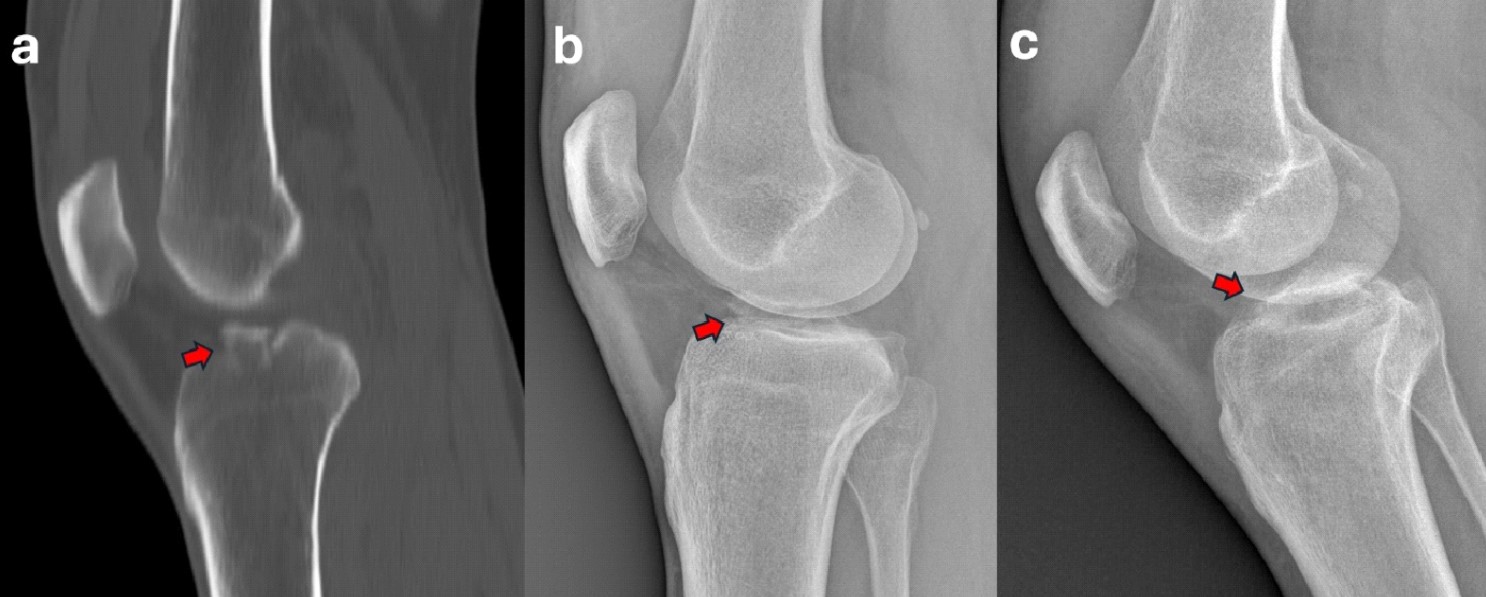

Conventional X-rays are often used as the initial diagnostic tool to identify fractures. CT scan is generally used in ambiguous cases and to better determine the degree of displacement4 (Figure 1). Based on that, the fracture can be classified according to the Meyers and McKeever’s classification in: Type I: minimally/nondisplaced fragment (< 3 mm); Type II: anterior elevation of the fragment; Type III: complete separation of the fragment (Type IIIa involves a small portion of the eminence; Type IIIb involves the majority of the eminence); Type 4: comminuted avulsion or rotation of the fracture fragment5. Alternatively, Green et al6 highlight the key role of MRI in the assessment of tibial eminence fracture because of the possibility to identify associated injuries such as meniscal tears (Figure 2) or ligamentous damage6,7. In our experience, additional soft tissue injuries such as meniscal entrapment or ACL injuries are identified alongside the fracture in a substantial number of cases8-10. The treatment approach depends on the severity of the fracture, with nondisplaced fractures often treated conservatively with immobilization in extension for 4-6 weeks11. However, in cases where there is a significant displacement, surgical intervention is typically required to prevent long-term instability, nonunion, or malunion12. Different surgical approaches have been proposed to manage tibial avulsion fractures. Among them, Arthroscopic Reduction and Internal Fixation (ARIF) has gained increasing preference over open techniques due to its minimally invasive nature, fast recovery times, and limited complications.

Figure 12. A 17-year-old male with a Meyers and McKeevers Type IV fracture (red arrow) in sagittal CT scan (a) and lateral radiographs (b). Radiograph at 6-week follow-up showing good reduction and healing of the fragment (red arrow) (c).

Figure 13. A 43-year-old male with a Meyers and McKeevers Type III fracture (red arrow) in sagittal CT scan (a) and lateral radiographs (b). Radiograph at 6-week follow-up showing good reduction and healing of the fragment (red arrow) (c).